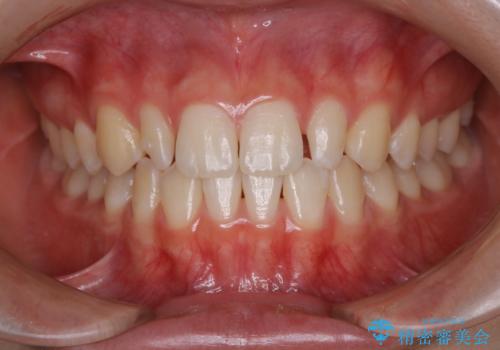

- 初診時、前歯部の見た目の改善を主訴にご来院されました。生まれつき歯が小さい状態の「矮小歯」とそれに伴う正中の「すきっ歯」があるため、大きなガタつきはないものの笑った時の印象に違和感が出る状態となっていました。

矮小歯が傾斜していることなどを踏まえ、より安全に治療を進めるために部分矯正を併用したセラミッククラウンでの治療を行うこととなりました。

今回のケースでは、歯が小さいだけでなく傾斜もしていたため補綴治療時に歯を削ることで神経の症状が出る可能性がありました。そのため、事前に部分矯正を行い歯軸の改善を行っておくことで、歯髄を温存することができました。